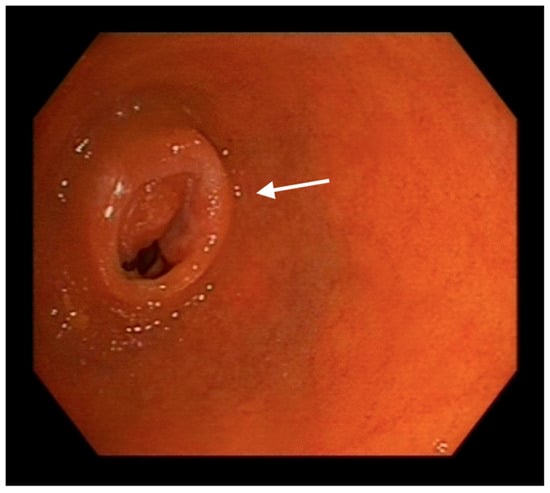

2. Case Presentation